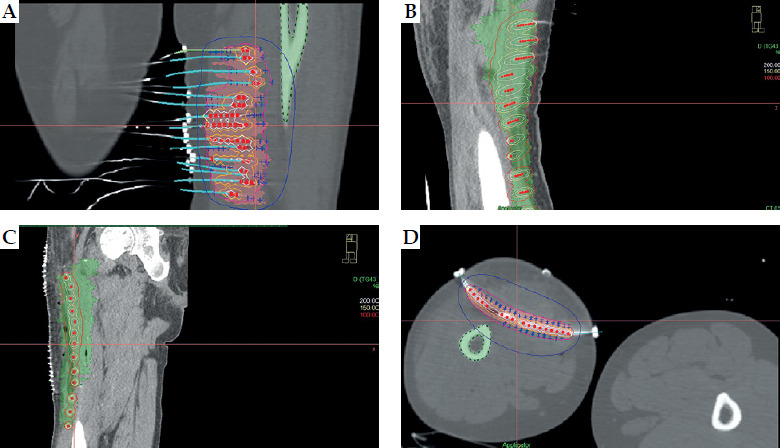

Material and methods: Seven patients with STS underwent conservative surgery and PHDRB between October 2020 and October 2023. PHDRB doses ranged from 3.0 to 3.5 Gy BID in 10 fractions, with or without subsequent EBRT, as indicated. EBRT was delivered in 4-5 weeks after surgical procedure at a dose of 45-50 Gy in 25 treatments, with daily dose of 1.8-2.0 Gy. Brachytherapy techniques and dosimetry guidelines were meticulously implemented to ensure optimal treatment delivery and minimize toxicity.